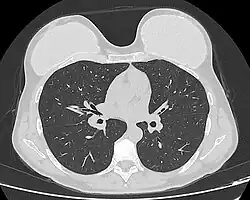

Silicone implant rupture can be evaluated using magnetic resonance imaging; from the long-term MRI data for single-lumen breast implants, the European literature about second generation silicone-gel breast implants (1970s design), reported silent device-rupture rates of 8–15 per cent at 10-years post-implantation (15–30% of the patients).[52][53][54][55] Additionally, high-resolution ultrasound is another effective method of evaluating silicone implant integrity.[56]

The study Safety and Effectiveness of Mentor's MemoryGel Implants at 6 Years (2009), which was a branch study of the U.S. FDA's core clinical trials for primary breast augmentation surgery patients, reported low device-rupture rates of 1.1 per cent at 6-years post-implantation.[57] The first series of MRI evaluations of the silicone breast implants with thick filler-gel reported a device-rupture rate of 1 percent, or less, at the median 6-year device-age.[58] Statistically, the manual examination (palpation) of the woman is inadequate for accurately evaluating if a breast implant has ruptured. The study, The Diagnosis of Silicone Breast implant Rupture: Clinical Findings Compared with Findings at Magnetic Resonance Imaging (2005), reported that, in asymptomatic patients, only 30 per cent of the ruptured breast implants are accurately palpated and detected by an experienced plastic surgeon, whereas MRI examinations accurately detected 86 per cent of breast implant ruptures.[59] Therefore, the U.S. FDA recommended scheduled MRI examinations, as silent-rupture screenings, beginning at the 3-year-mark post-implantation, and then every two years, thereafter.[25] Nonetheless, beyond the U.S., the medical establishments of other nations have not endorsed routine MRI screening, and, in its stead, proposed that such a radiologic examination be reserved for two purposes: (i) for the woman with a suspected breast implant rupture; and (ii) for the confirmation of mammographic and ultrasonic studies that indicate the presence of a ruptured breast implant.[60]